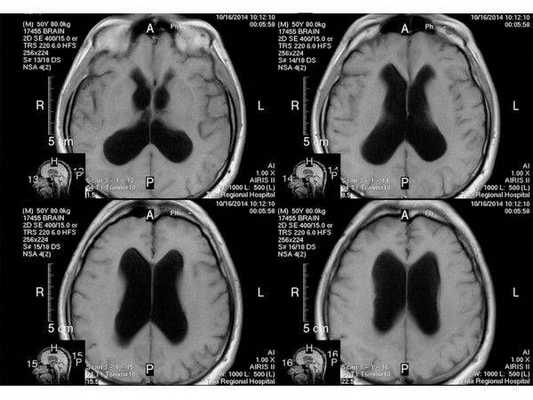

- С помощью диагностической визуализации — компьютерной томографии (КТ) и магнитно-резонансной томографии (МРТ) — получают детализированные изображения головного и спинного мозга. Врачи могут увидеть размеры и расположение опухоли и лучше понять, какие участки мозга оказались затронуты. МРТ часто предпочтительнее, поскольку обычно обеспечивает более четкую визуализацию опухолей головного мозга.

Наиболее информативными и точными методами диагностики краниофарингиомы являются МРТ и КТ головного мозга. При помощи данных методов исследования специалисту удается получить послойное изображение мозговых тканей, что позволяет наиболее точно определить место локализации патологического процесса, размеры образования, структура и форму опухоли, ее расположение относительно окружающих тканей.